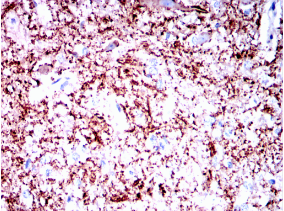

SYT1 Mouse Monoclonal antibody[8G11]

SYT1: synaptotagmin I. The synaptotagmins are integral membrane proteins of synaptic vesicles thought to serve as Ca(2+) sensors in the process of vesicular trafficking and exocytosis. Calcium binding to synaptotagmin I participates in triggering neurotransmitter release at the synapse.

IHC    1/200 - 1/1000